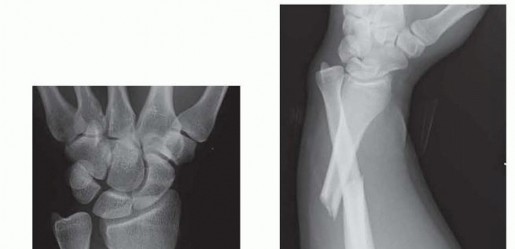

DEFINITION Fracture of the radial shaft with an associated distal radioulnar joint (DRUJ) dislocation (FIG 1A…